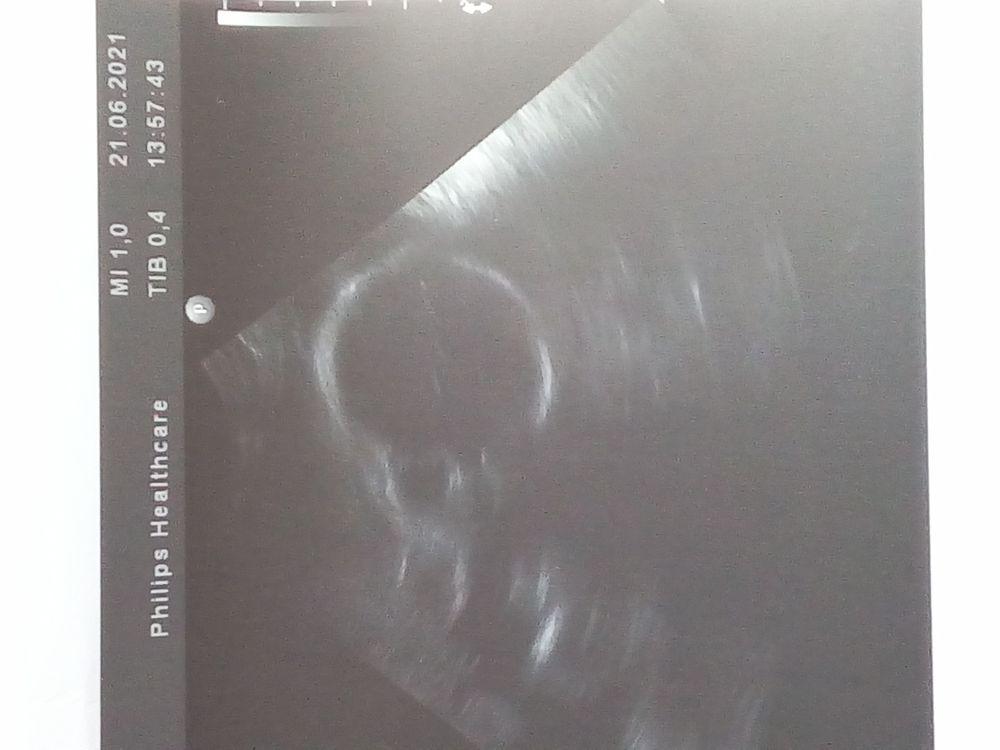

УЗИ 27 недель

УЗИ, КТГ, доплерВот мы и увидились с малышкой, хомячок щекастый , уже весит 1100 г. Длина шейки матки в норме, надеюсь не укоротится до ПДР. Снова сидит на попе, но думаю ещё рано делать выводы, позже перевернется. Про обвитие пуповиной шеи плода, места много ещё пока, может размотается, да даже если нет, это не проблема, в родах петлю снимают.